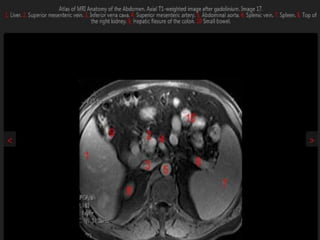

MRI anatomy images of the abdomen.

MRI anatomy imagesof the abdomen.